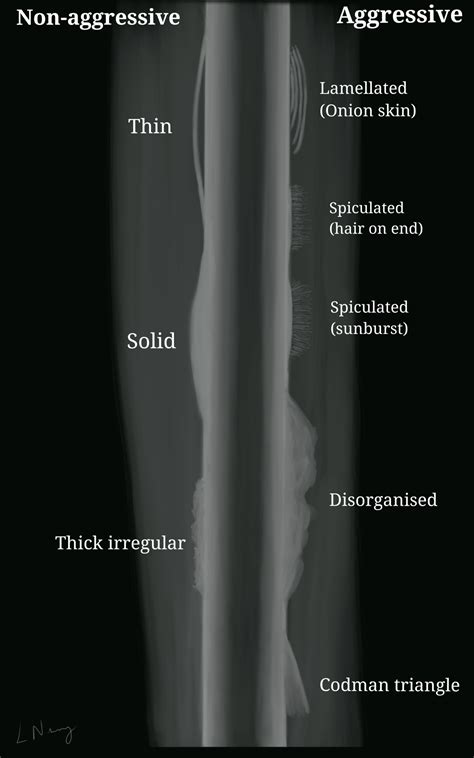

Imaging tests, such as X-rays, CT scans, and MRIs, can help identify the location and extent of the cancer. These tests can also provide information about the bone structure and any potential fractures or deformities. However, imaging tests alone are not sufficient for a definitive diagnosis.